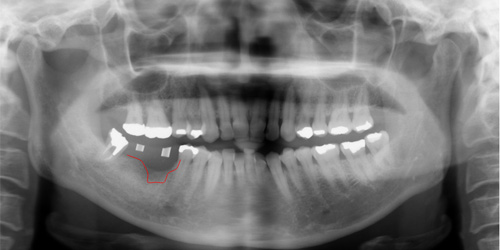

治療前のレントゲンです。しろい筒の位置にインプラントを埋入しますが、手前の位置の骨が喪失(赤線)してます。

奥の親知らずまったく咬合せず、ブリッジの土台になりません。